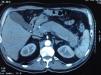

ImagenAl realizar una tomografía computarizada (TC) o resonancia magnética (RM), el aumento difuso de la glándula pancreática, con bordes uniformes y realce tardío, con/sin anillo tipo cápsula es un hallazgo muy sugestivo de PAI (fig. 1). Esta imagen, llamada «páncreas en salchicha», solo se da en el 19-27% de la PAI24. Ante este hallazgo el diagnóstico diferencial debe establecerse con el adenocarcinoma pancreático. Otro hallazgo puede ser la presencia de un engrosamiento focal. Son imágenes sugestivas de malignidad las masas de baja densidad, la dilatación del conducto pancreático con amputación brusca del mismo a nivel de la masa pancreática, así como la atrofia pancreática distal20.